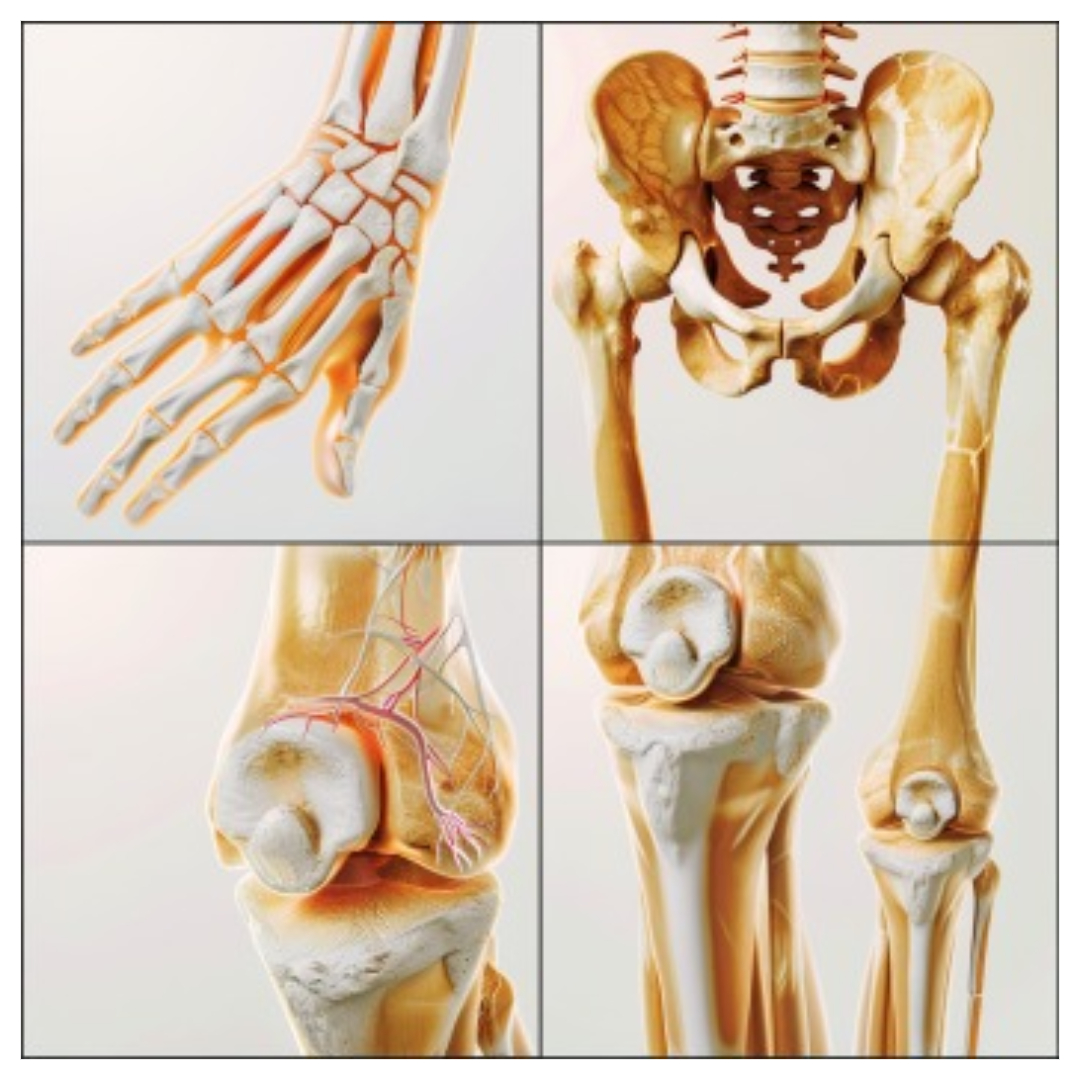

2. 관절의 변형 시작

손가락이나 발가락 같은 작은 관절에서 시작하여, 뼈가 조금씩 변형되기 시작합니다. 이때 손가락이 약간 휘어지거나, 발가락이 비틀 어지 듯한 변형이 관찰될 수 있습니다.

1. 심각한 관절 변형

손가락, 발가락뿐만 아니라 손목, 무릎 등의 관절에도 변형이 일어납니다. 관절이 휘어지거나 부러지듯 변형되며, 외관상으로도 뚜렷이 보이게 됩니다.

2. 근육 위축

3. 기능 상실

관절이 완전히 손상되면 더 이상 움직일 수 없게 됩니다. 관절 내 연골이 닳아 없어지거나, 뼈가 직접 맞닿는 상황까지 이르기도 하며, 이로 인해 심한 통증과 함께 기능 상실이 발생합니다.